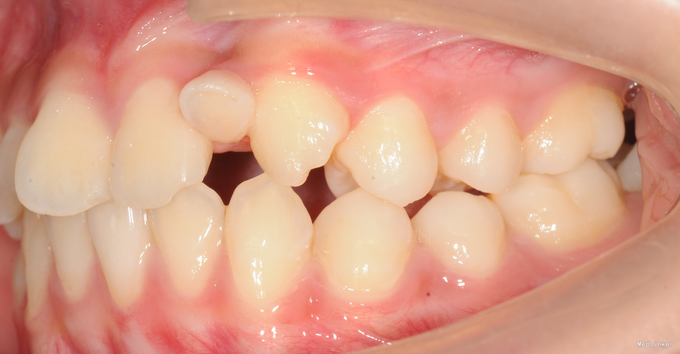

13岁女孩,主诉门牙不美观,要求改善

直面型,左上乳2仍存,口内未见恒2,下前牙口内只有3颗。上下牙齿轻度拥挤不齐。全景示下前牙先天缺失一颗,左上恒2垂直埋伏阻生。